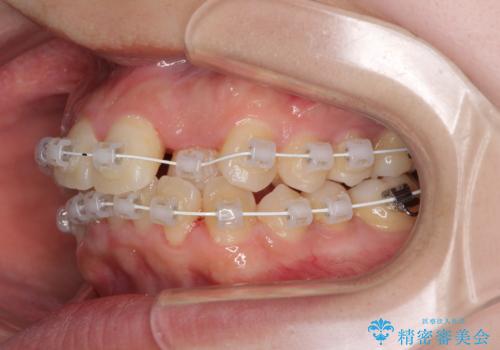

短期間で終了 デコボコをワイヤー矯正で解消

- 審美装置

- 治療期間

- 1年3ヶ月

- 上下のデコボコと前歯のクロスバイトを改善したいとのことで来院された患者様です。

極力短期間で治療したいとのことで、ワイヤー装置による矯正治療を行うこととしました。

マウスピースによる矯正治療も提案しましたが、ご自身でのマウスピースの管理の面倒くささと、なるべく早く治療を終えたいとのことで、ワイヤー矯正を選択されました。